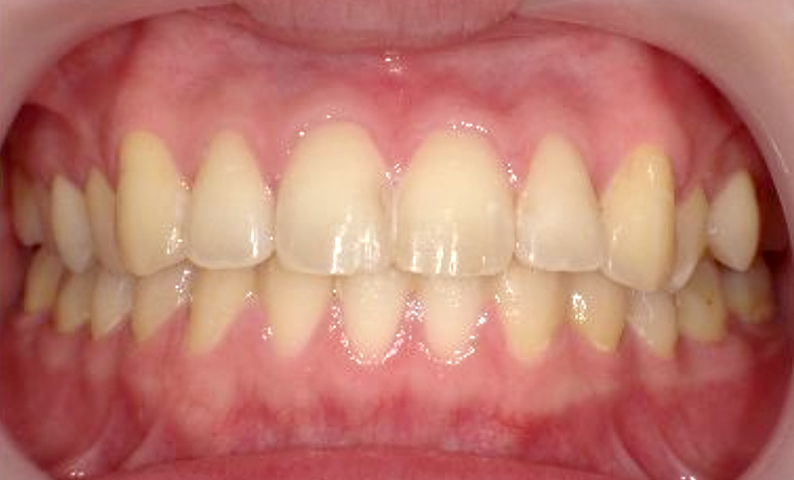

症例_001 前歯「捻転歯」症例

治療期間:6ヶ月金額:48万円+税20代女性少しのねじれ捻転歯下の八重歯

| Before | After |

|---|---|

|